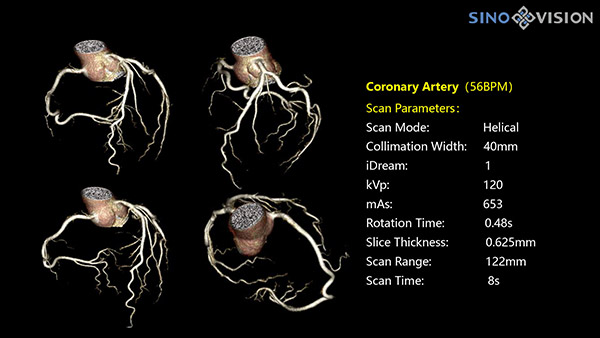

Инновационный 128-срезовый компьютерный томограф SinoVision InsitumCT 568 – это сочетание высокой скорости работы, низкой дозы и максимума возможностей для подавляющего большинства клинических случаев, как в рутинных, так и в углубленных специализированных исследованиях, в том числе педиатрические и кардиологические исследования при сверхнизких дозах.

Полнофункциональная платформа клинической диагностики может точно определять местонахождение и диагностировать общие повреждения качественно и количественно, а также достигать полнофункциональных клинических показателей, включая обширные кардиологические исследования со сверхнизкими дозами лучевой нагрузки.

- Минимальное время одного оборота рентгеновской трубки: От 0.48 до 2 сек

- Коронарный анализ

- Ретроспективный режим сканирования с ЭКГ-синхронизацией

- Проспективный режим сканирования с ЭКГ-синхронизацией

- Режим последовательного сканирования c ЭКГ-синхронизацией и без ЭКГ-синхронизации